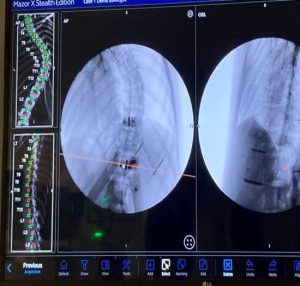

Α. Πέραν της βελτίωσης του συστήματος Αξονικής Πλοήγησης (O-ARM) με συστήματα 2ης γενιάς, εισέρχεται στη χειρουργική η χρήση της Ρομποτικής Χειρουργικής (Robotic Surgery).

Λόγω τεχνικών θεμάτων δεν υπερέχει η Ρομποτική Χειρουργική ουσιαστικά μέχρι σήμερα εκείνης όπου γίνεται χρήση του O-ARM. Αμφότερες οι εφαρμογές έχουν τη δυνατότητα να βοηθούν στην ακριβή τοποθέτηση των βιδών της σπονδυλοδεσίας, συγκεκριμένα στο πέρασμα των βιδών από τους μίσχους των σπονδύλων. Υπάρχουν ωστόσο ορισμένες διαφορές και ομοιότητες :

- Τα ποσοστά ακριβείας είναι περίπου τα ίδια.

- Εφαρμόζονται στις ίδιες επεμβάσεις.

- Δίνουν τη δυνατότητα να πραγματοποιούνται «ανοικτές» και «κλειστές» επεμβάσεις στη Σπονδυλική Στήλη.

- Το κόστος των Ρομποτικών Μηχανημάτων είναι μεγαλύτερο.

- Ο χρόνος εκμάθησης του Ρομποτικού συστήματος είναι μεγαλύτερος.

- Προς το παρόν ο χειρουργικός χρόνος στις Ρομποτικές επεμβάσεις είναι μεγαλύτερος

- Η προσλαμβανόμενη ακτινοβολία μάλλον είναι μικρότερη με το Ρομποτικό σύστημα.

- Ωστόσο, με τη χρήση του Ρομποτικού συστήματος μπορεί να γίνει καλύτερος προεγχειρητικός σχεδιασμός για τις διορθώσεις των σπονδυλικών παραμορφώσεων.

Εικόνα 4: Διεγχειρητική φωτογραφία (α) υπό την καθοδήγηση του ρομποτικού συστήματος. Γίνεται η τοποθέτηση της διαυχενικής βίδας εντός του σπονδυλικού σώματος.

Εικόνα 6 (α,β,γ): Ρομποτική χειρουργική για διόρθωση σκολίωσης της σπονδυλικής στήλης.

α. Με την χρήση ρομποτικού συστήματος, διαυχενικές βίδες έχουν τοποθετηθεί εντός του σπονδυλικού σώματος.

β. Διεγχειρητική ακτινογραφία του σκολιωτικού κυρτώματος, προ της διόρθωσης.

γ. Μετά την πραγματοποίηση των ενδεοκνυόμενων χειρισμών και την τοποθέτηση των ράβδων έχει επιτευχθεί πλήρης αποκατάσταση της σπονδυλικής στήλης στο φυσιολογικό προσθιοπίσθιο επίπεδο.